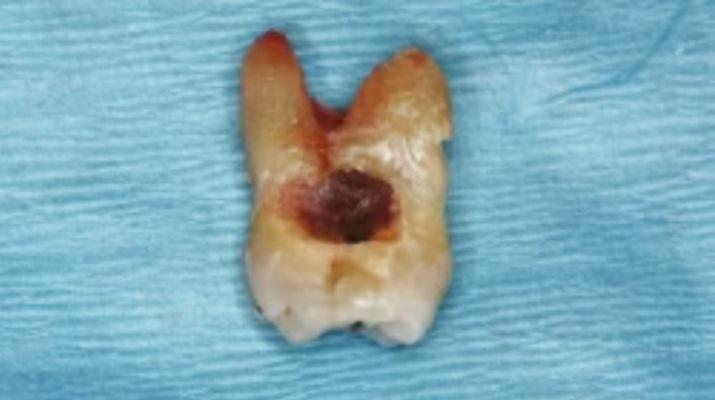

Примерно через 19 месяцев ортопантомограмма выявила кариозные поражения на нескольких зубах. Два коренных зуба на верхней челюсти не поддавались восстановлению, и их пришлось удалить. На еще одном зубе было проведено эндодонтическое лечение и установлена металлокерамическая коронка.